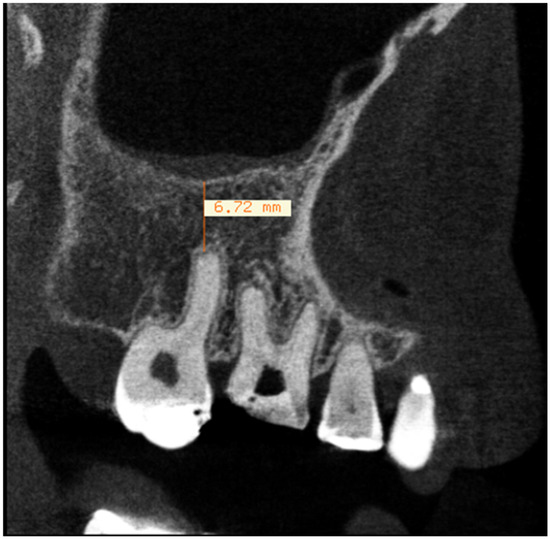

2. Materials and Methods

2.1. Evaluation of Dental Parameters